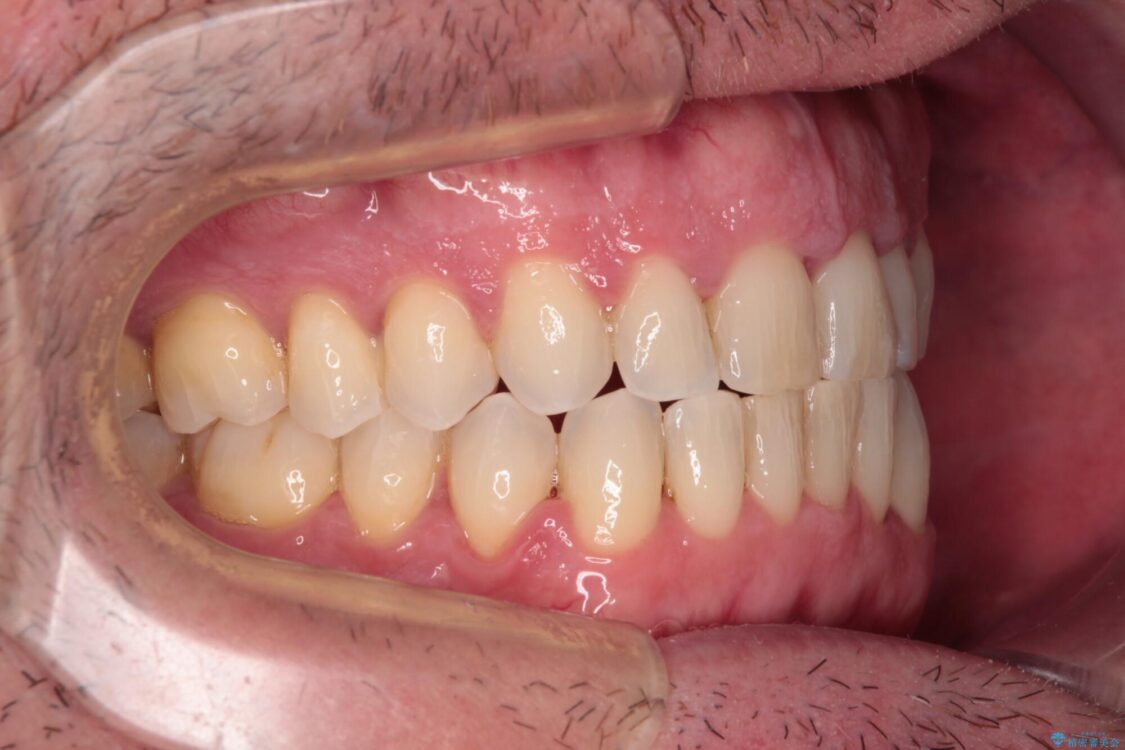

時間はかかりましたがトレーニングを頑張ってくださり、無事に前歯を接触させることができました。

治療後

• 前歯でものを噛みきりたい 目立たない装置でのワイヤー矯正 治療後画像